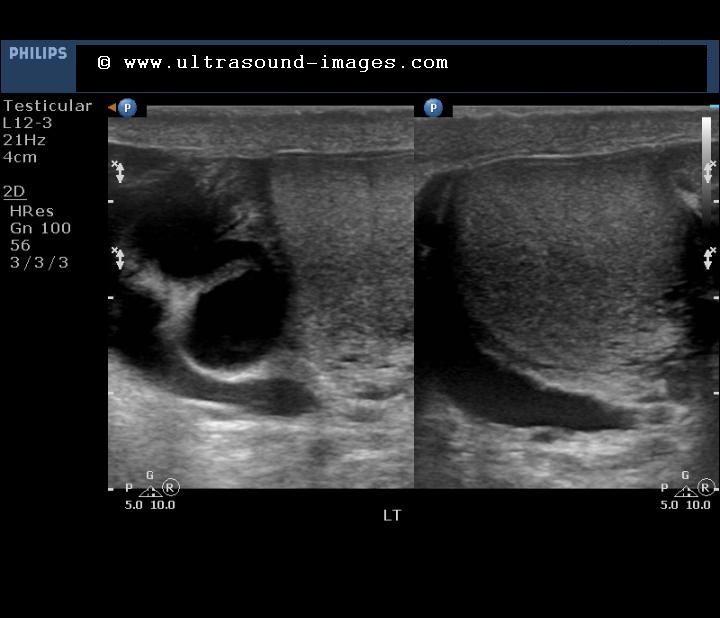

Both kidneys are shown in the ultrasound image below with typical changes described about:

Colour Doppler images of the left and right kidneys show diminished vascularity in both kidneys. This is an ominous sign and signifies and imminence of end-stage renal disease in the not too distant future.